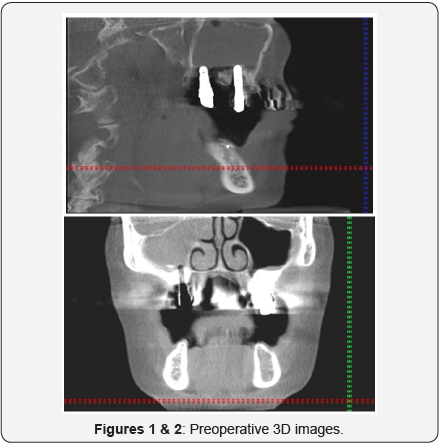

A 60-years old female patient referred to our Clinic with an oroantral fistula on the right side after SLP and implantation in 2008. From the anamnesis there was reported a late implantation in 2003 alio loco with external sinus lift after trauma related to a bicycle accident in 1980. Between the accident and the first implantation the patient was treated with crowns and bridges. After two years of severe facial pain she applied for removal of the implant. In 2008 free of pain underwent a second implantation. Since the operation mentioned increased facial pain localized at the operated side (Figures 1 & 2).

The clinical Examination showed except the severe pain in the region of 15 and the oroantral fistula with drain of pus, no evidence of an acute sinusitis. The peirimplant probing depth measurements revealed a severe periimplantitis with immediate connection to the sinus floor. Additionally the implants 17 and 27 showed an untreatable periimplantitis with bone loss of 5mm. According to the performed trigeminal tests was no evidence of trigeminal neuralgia. The 3D radiology examination without contrast revealed an opaque appearance, capturing the whole right maxillary sinus. The Patient had a medical history of Hashimoto-thyroiditis and TIA.